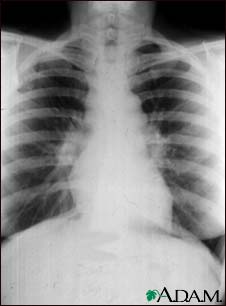

Sarcoid, stage I - chest X-ray

Sarcoid is primarily a lung (pulmonary) disease. In the early stages, a chest film may show enlargement of lymph nodes in the center of the chest near the heart (mediastinum).